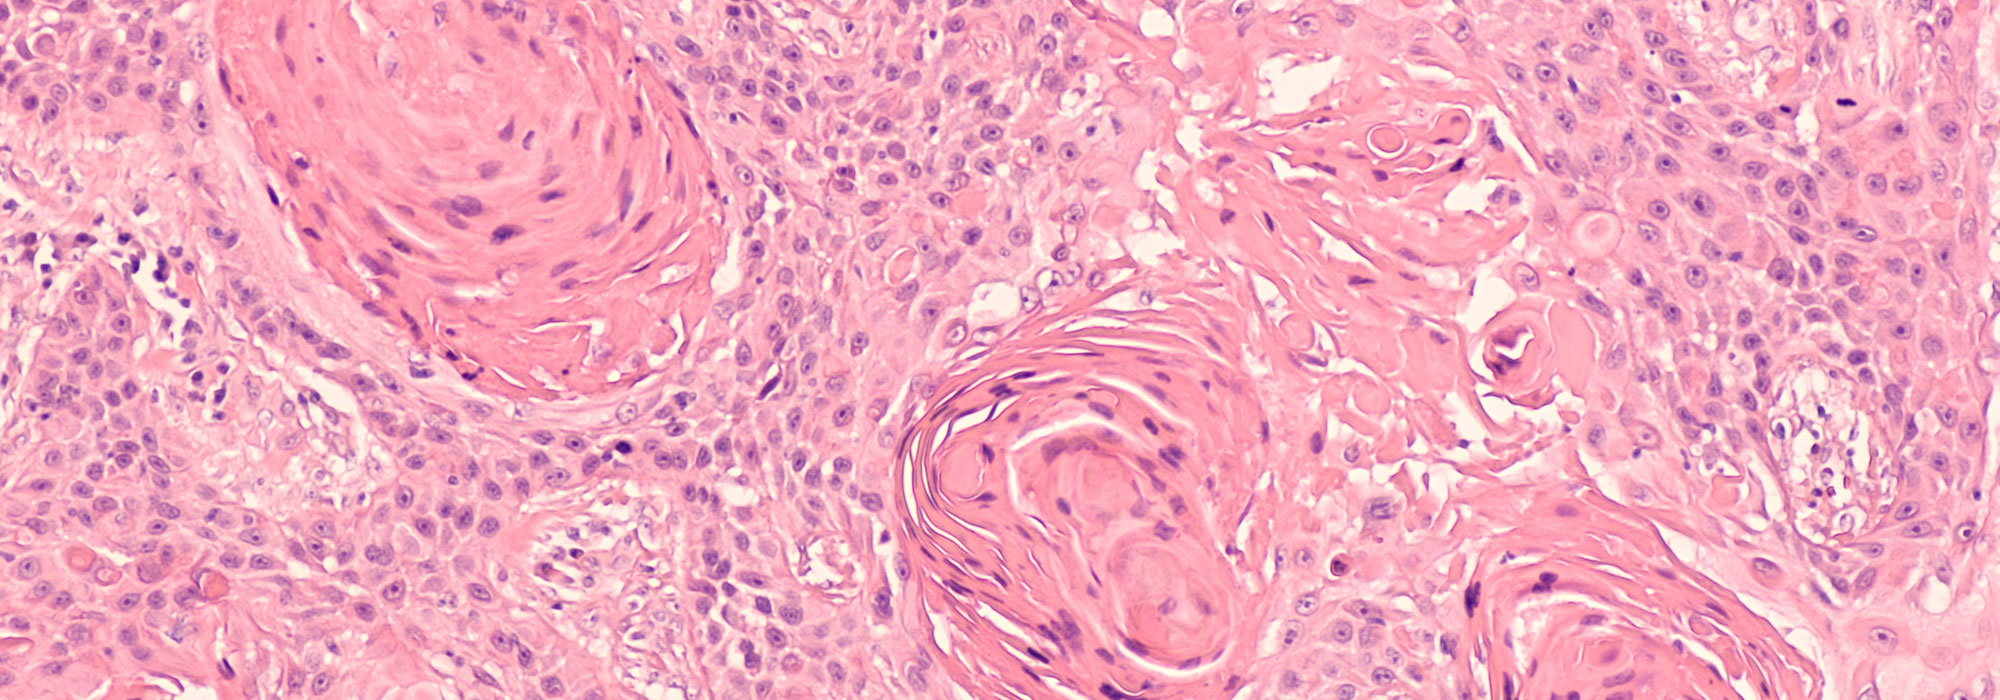

Viele Tumore sehen auf den ersten Blick gleich aus, unterscheiden sich aber in Ihrem Wachstum und der Metastasierungsrate stark. Daher ist eine genaue, möglichst frühzeitige Diagnose und somit eine Klassifizierung des Tumors essenziell. Hierzu sind häufig bildgebende Untersuchungen (Röntgen, Ultraschall), sowie die Untersuchung von Gewebeproben notwendig. Feinnadelaspirationen können in der Regel am wachen Patienten entnommen werden, wohingegen für Biopsien meistens eine kurze Narkose notwendig ist. Im weiteren Verlauf werden diese Gewebeproben histologisch oder zytologisch untersucht. Dazu arbeiten wir eng mit renommierten Histologen zusammen. Auch Blutuntersuchungen können uns auf ein neoplastisches Geschehen hinweisen.